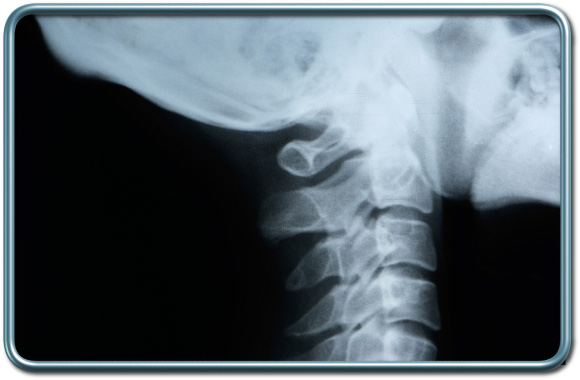

למינקטומיה צווארית-Cervical laminectomy

סוג הרדמה- כללית, לעיתים, כשיש הגבלה קשה של התנועה הצווארית או סיכון להחמרת השפעה נוירולוגית בתנועות צוואריות יתכן צורך בצנרור קנה בעירות (תחת הרדמה מקומית של נתיב האויר) וזאת על מנת לבצע הערכה נוירולוגית חוזרת לאחר השכבת החולה וכן על מנת להמנע מתנועות צוואר מוגזמות תוך צנרור הקנה. אמצעי הניטור נגזרים ממחלות הרקע של החולה. בנוסף לכך לעיתים נעשה שימוש בניטור נוירופיזיולוגי המאפשר זיהוי פגיעה במסלולים עצביים חשובים תוך כדי הניתוח.